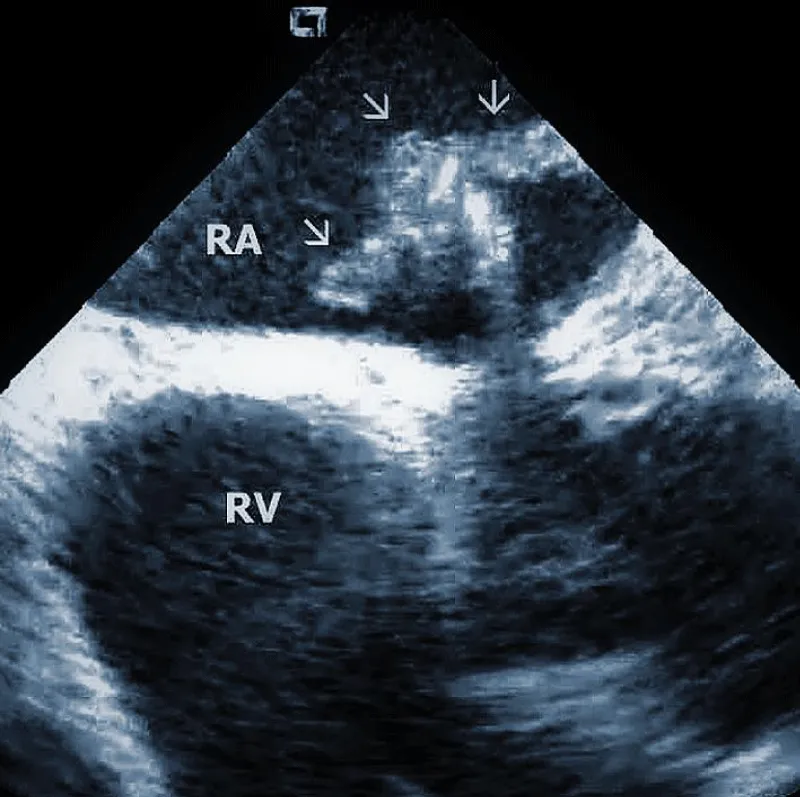

Lead adherent echo densities (LAE): ICE allows visuali-zation of the leads and echo densities adherent to them. In our experience, LAE can be detected in the majority of patients (Figure 2A). One recent study revealed LAE in 72% of cases [10]. Locations of LAE were the superior vena cava (16%), its junction with the right atrium (11%), right atrium (57%), and tricuspid annulus (16%). Finding LAE opens the question of their clinical importance. Interestingly, Ho, et al. systematically performed TEE before TLE, which was performed for non-infectious indications in 108 consecutive patients [11]. The authors reported an 18.5% incidence of lead thrombi, all of which were < 2 cm. This figure is significantly less than in the above study. This discrepancy can be explained by the higher resolution and superior maneuverability of ICE compared to TEE [12].

Figure 2A: Depiction of the lead adherent echodensity (arrows) floating on the ICD lead in the right ventricle (RV).

Therefore, ICE could be essential in patients with a suspected diagnosis of infective endocarditis since it necessitates the removal of the entire pacemaker or ICD system. Narducci et compared ICE with TEE to detect TLE in the setting-related infective endocarditis [13]. ICE identified the presence of intracardiac masses in all 58 patients (100%), whereas TEE identified the presence of ICM in only 38 patients (65%). The authors concluded that ICE is a useful technique for diagnosing intracardiac masses, thus providing improved imaging of right-sided leads and increasing the diagnostic yield compared with TEE. The pretest probability of infective endocarditis determines the incremental diagnostic value of ICE in infection of implantable devices. If the diagnosis of endocarditis is clinically rejected, even ICE does not improve the clinical decision-making process. The best diagnostic value of ICE was found in patients with a probable diagnosis of endocarditis. We recently had an ongoing pilot project focused on biopsies from TLE using a bioptome and ICE guidance. In anecdotal cases, it helped to establish the diagnosis of infective endocarditis.

Technically speaking, the presence and size of intracardiac masses in patients suspected of infective endocarditis are critical in planning TLE procedure (Figure 2B). Large vegetations were found more common in patients with renal failure, heart failure, ICD system, and loops of the leads [14]. In another study, diabetes was related to larger vegetations, similarly younger age. Anticoagulation therapy resulted in smaller vegetations [15].

Figure 2B: Large vegetation floating on the ICD lead in the Right Atrium (RA). RV: Right Ventricle.